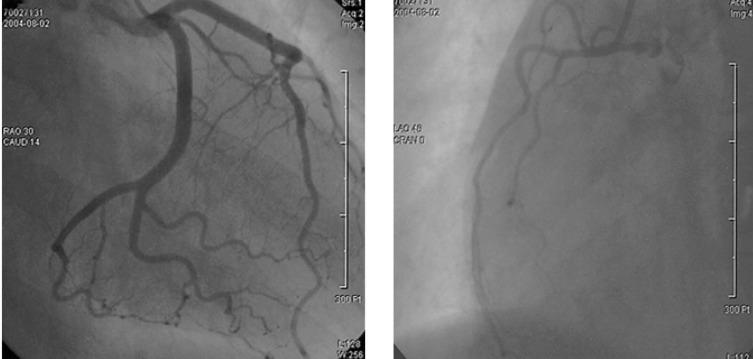

Maternal septic shock and disseminated intravascular coagulation (DIC) following amniocentesis is a relatively rare condition, and its incidence is only 0.03 approximately 0.19%. Acute myocardial infarction (AMI) associated with DIC is also rare. We report here on a 40-year-old female patient who had septic shock and DIC that was complicated by AMI following amniocentesis. The possible mechanism of AMI in this patient may have been coronary artery thrombosis associated with DIC.

羊膜腔穿刺术后发生的产妇感染性休克和弥散性血管内凝血(DIC)是一种相对罕见的病症,其发病率仅约为0.03%至0.19%。与DIC相关的急性心肌梗死(AMI)也很罕见。我们在此报告一名40岁女性患者,她在羊膜腔穿刺术后发生感染性休克和DIC,并并发AMI。该患者发生AMI的可能机制可能是与DIC相关的冠状动脉血栓形成。